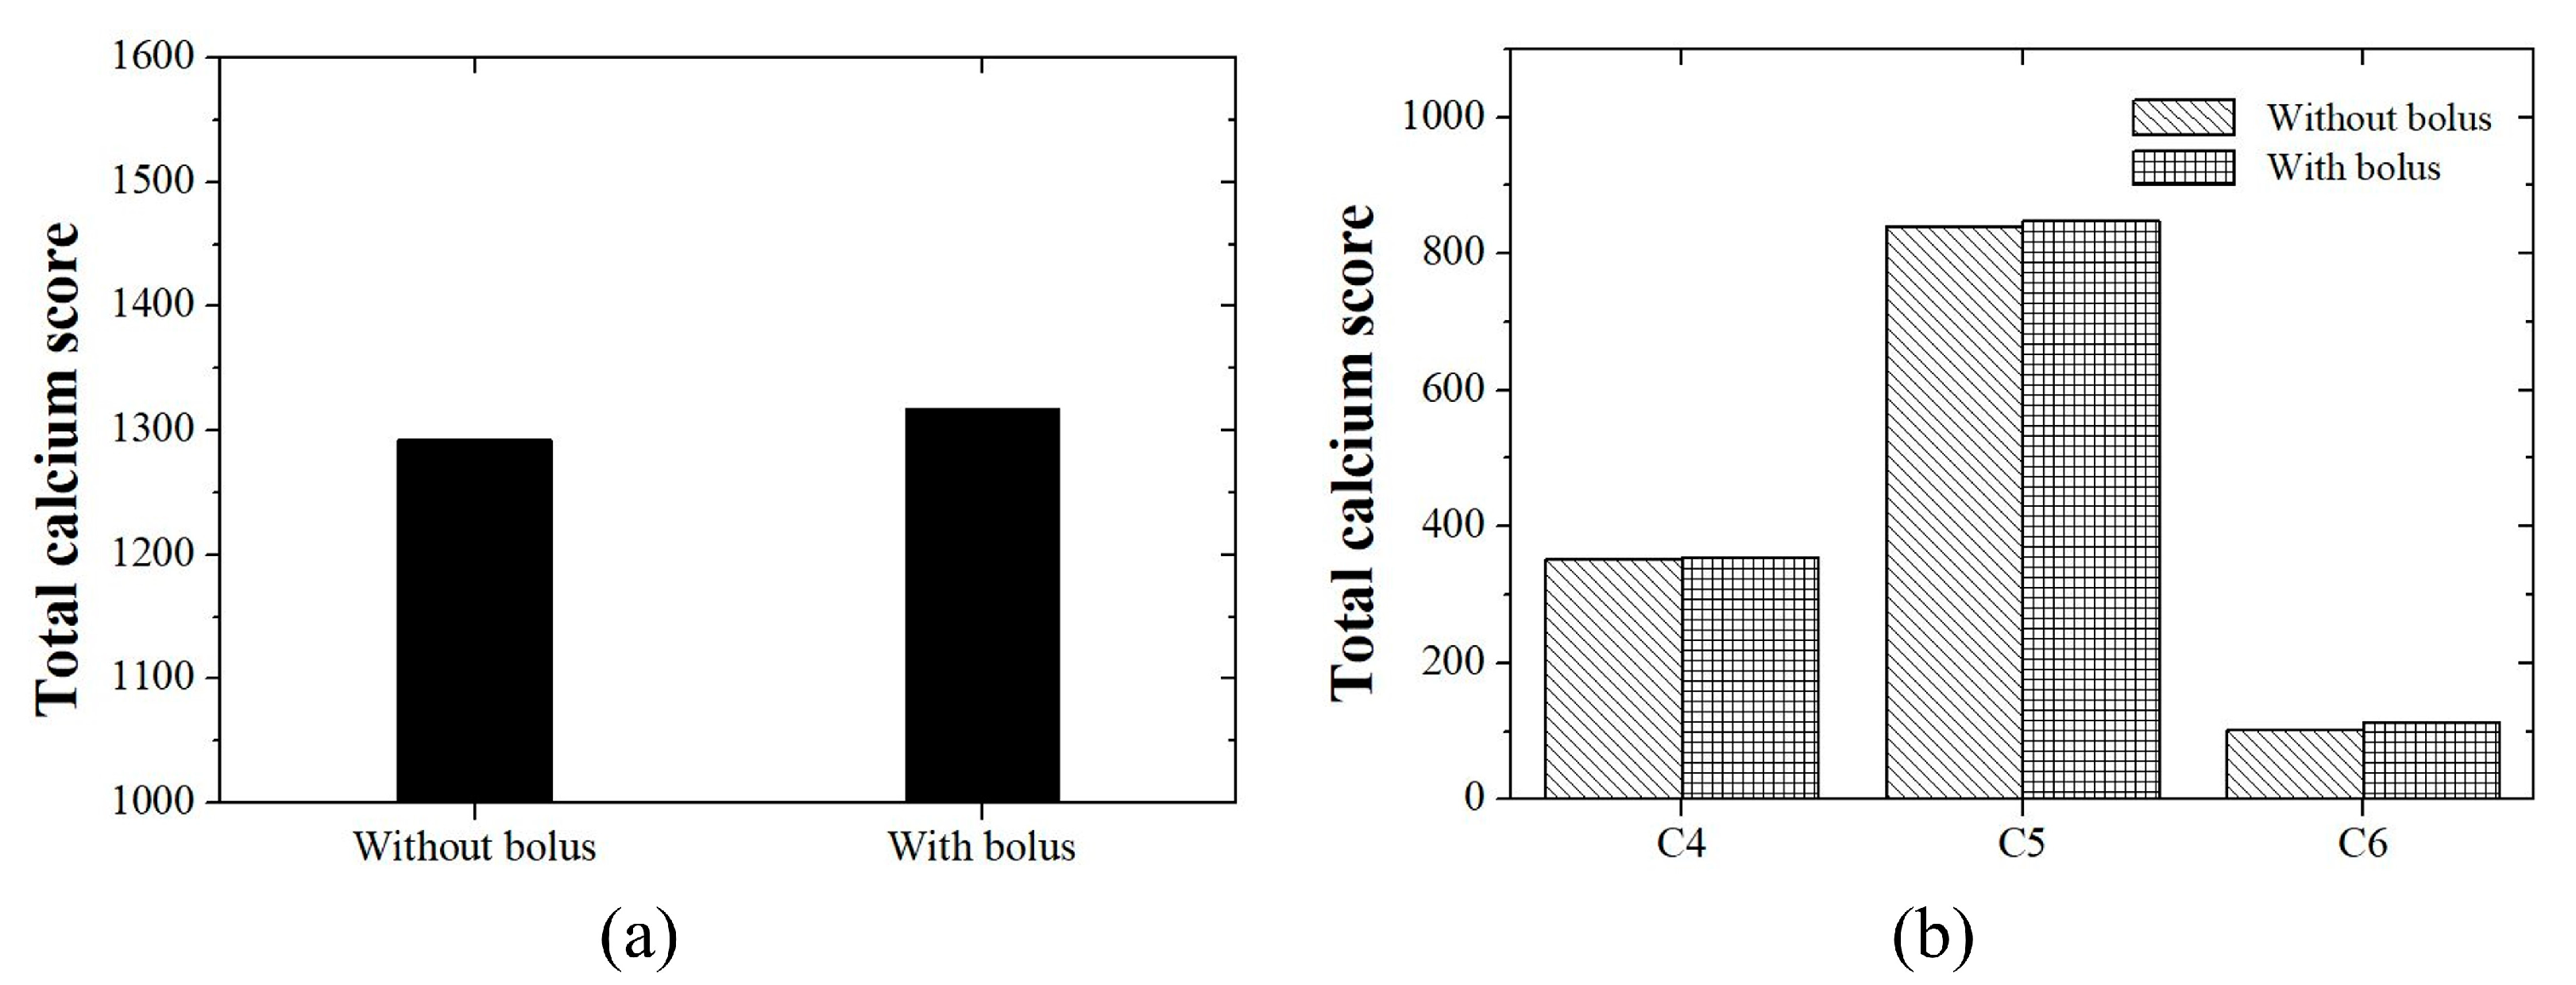

2.4. Phantom Study

3. Results

3.2. Phantom Study

4. Discussion